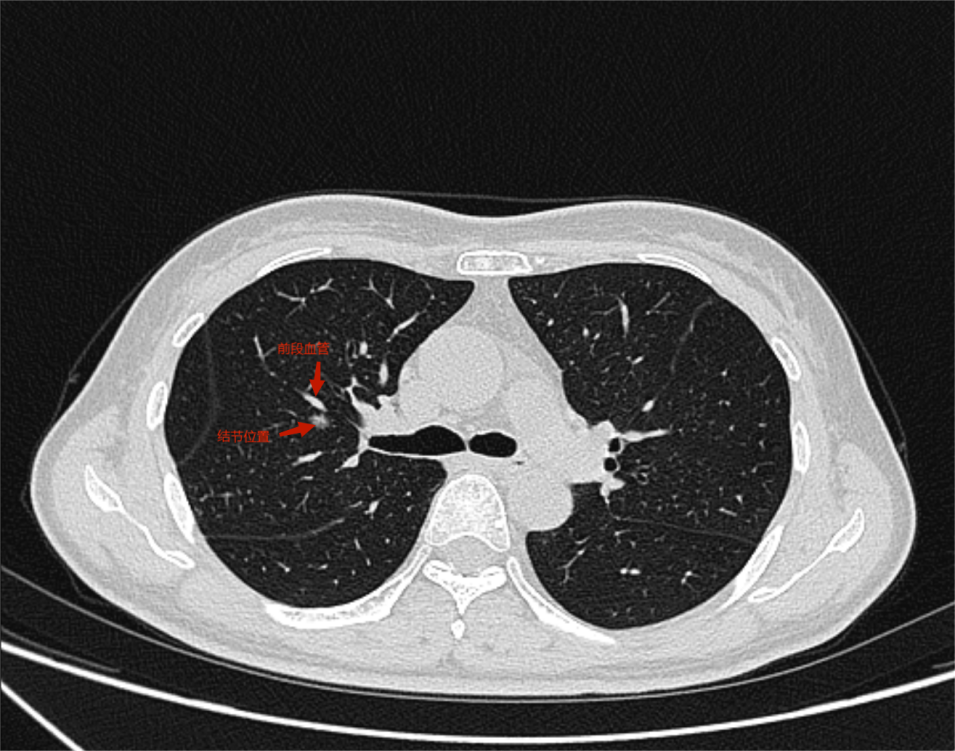

经随访观察半年后,在复查时发现结节增大至8mm,考虑早期恶性肿瘤可能性大,胸外科侯向生主任团队在详细阅读胸部CT后,确定结节位置及靶肺支气管、肺动、静脉情况,发现其结节位于右肺上叶前段与后段交接处,位置较深。结合病人意愿和病情现况,侯向生主任团队在保留肺功能和完整切除肿瘤间抉择出最优手术方案--右肺上叶前段切除。

(术前胸部ct)